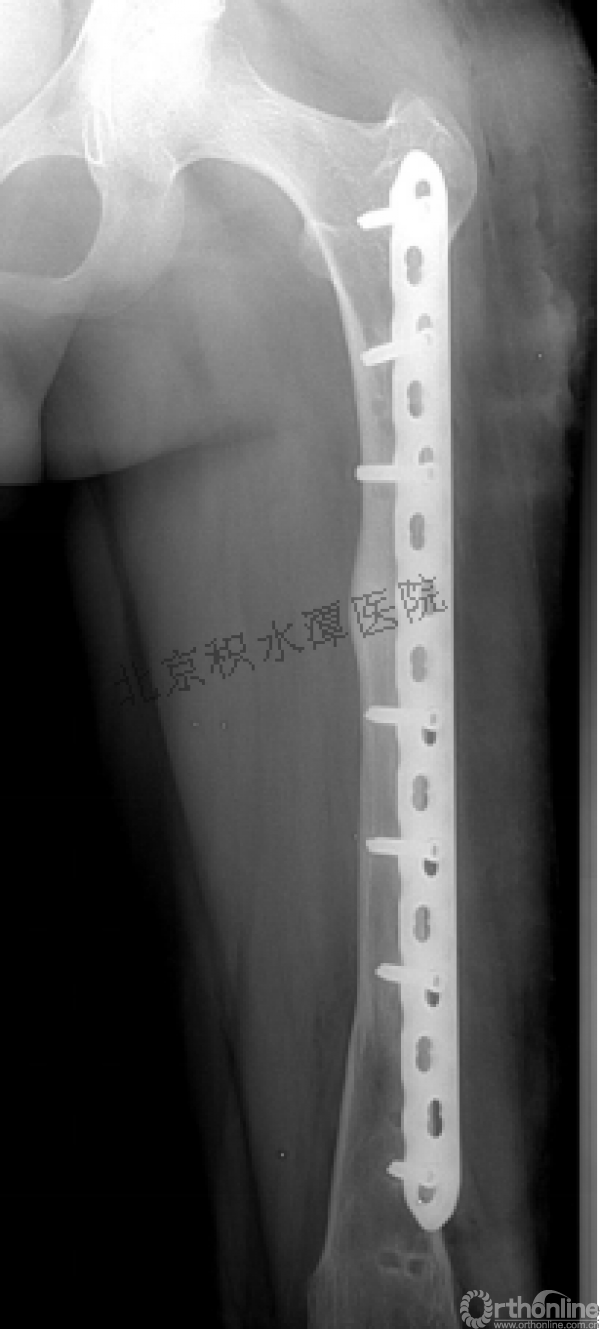

病例分享一

男孩 、5岁,初次骨折于2007年7月。

术后2年→再骨折→再次手术

钢板固定后一年

取板后再骨折→TEN

TEN取出后2个月

闭合复位再固定加尾帽

又过了4年!时间来到2015年

一年以后顺利愈合,实则危机四伏

数月后再骨折!牵引!

髋人字支具

外固定架术后一年

整整11年!是否治疗终结?

病人的付出?医生当反思!